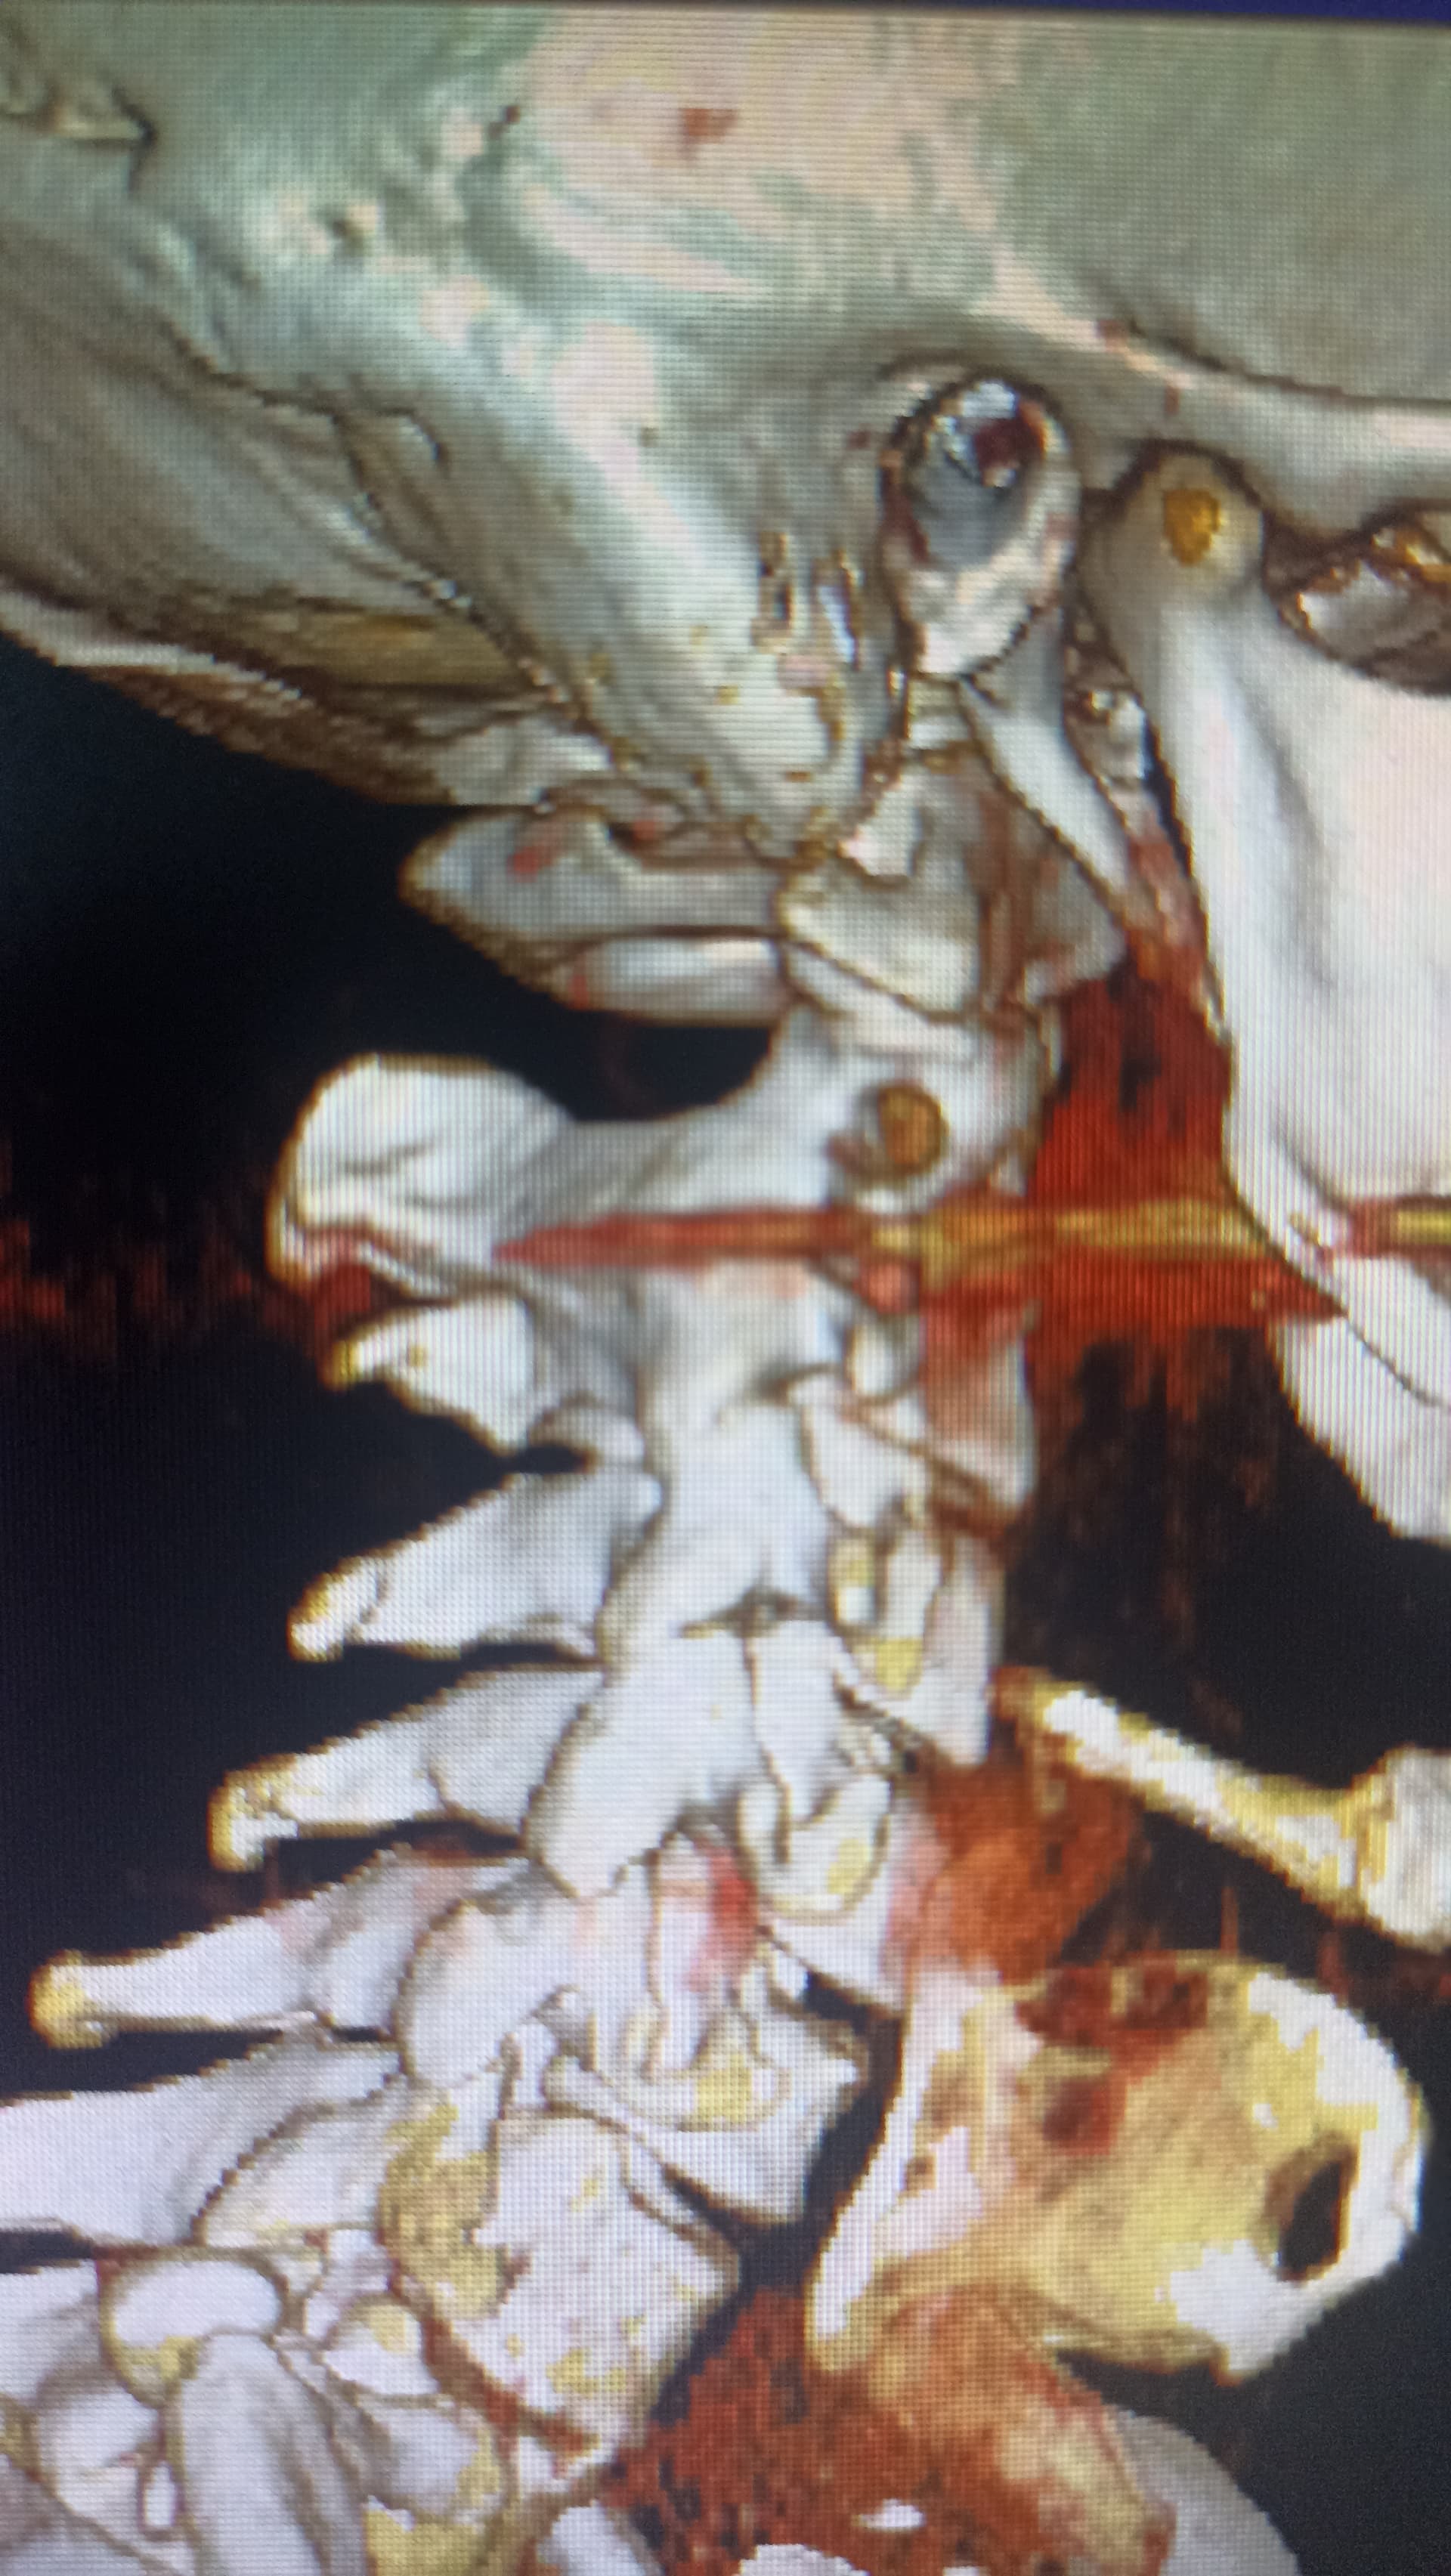

Hopefully these images can give a better view

Regarding your styloids, both look thick at the top & very angled. The tip of the right one looks very pointed. I can’t see the tip of the left one. They don’t look super long but the angle & thickness could definitely be plying into your symptoms.

Hopefully others with more knowledge will comment, I can’t see any obvious compression, but sometimes just the styloid touching an artery can be enough to irritate it & cause symptoms, I may be wrong but the hyoid on the left side looks quite close to the carotid bifurcation, where the carotid artery divides into internal & external arteries, this is just a guess though…

Good call, @Jules! Actually, I think the hyoid looks close to the carotid bifurcation on both sides & may even be poking it on the right side.

The left side is very similar so I didn’t annotate it.